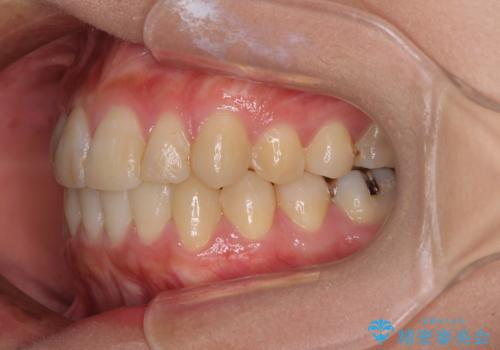

- 上下の八重歯を気にして来院された患者様です。

八重歯の後ろの歯を1歯抜歯し、補助装置(リンガルアーチ)を用いて八重歯の位置を改善し、その後インビザラインにより矯正治療を行うこととしました。

右側のみ上下小臼歯を抜歯したため、上下の正中が右にずれてしまう可能性があります。

また、元々右側は上下が咬み合っていないため、矯正をしても咬み合わないことも考えられました。

治療期間はかかりましたが、正中も合い、綺麗な仕上がりとなりました。